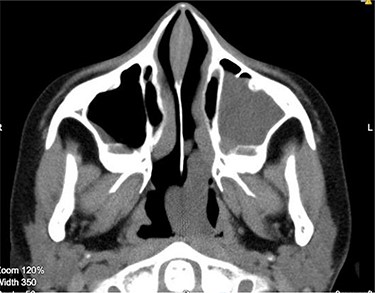

Medialization of the middle turbinate was done followed by an uncinectomy. The cystic nasal component was removed using blakesley forceps and a middle meatal antrostomy was done (Fig. 4).

Both the cystic and the solid components of the ACP can be visualized as it has removed from left nasal cavity.